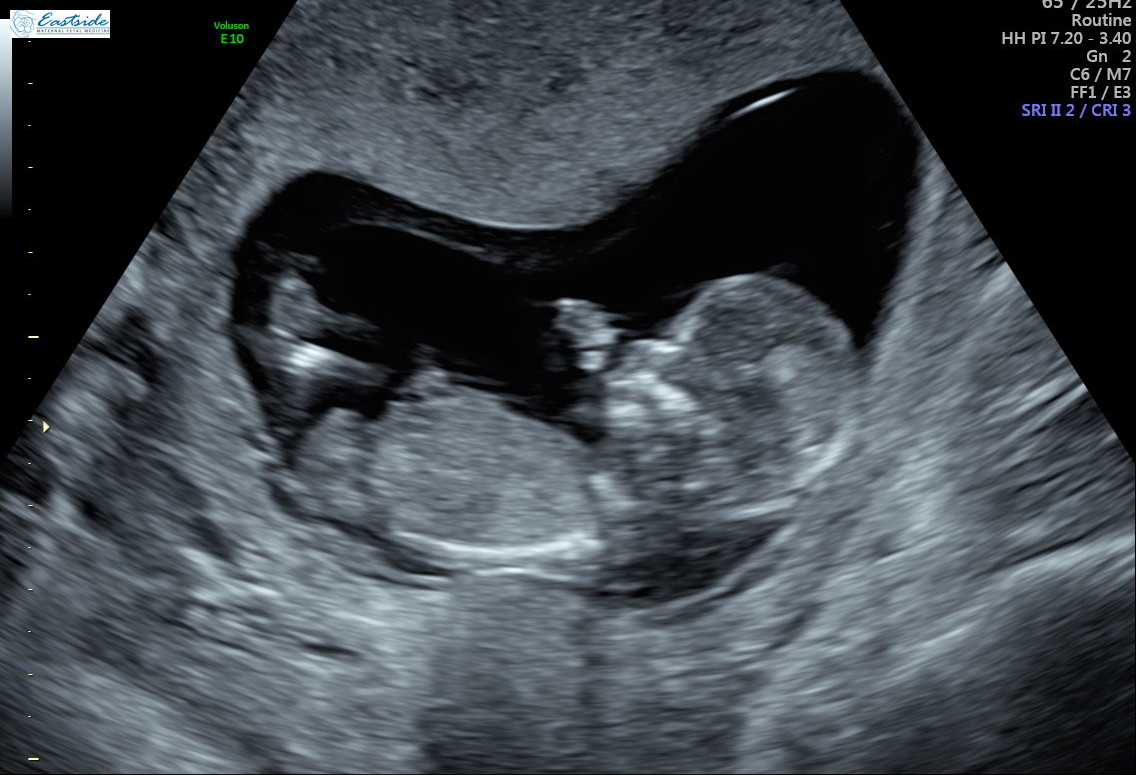

I am wondering if any experts or experienced could review the pics from my 13 week ultrasound? The tech said she was 80% sure of gender, but is it obvious to any of you? We have 3 girls so as you might guess, we are a bit anxious to find out!

Thanks! Attachment 38878Attachment 38879Attachment 38880Attachment 38881Attachment 38882Attachment 38883